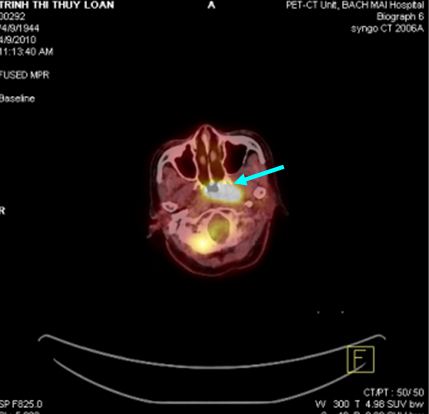

Trước điều trị: khối u vòm lớn tăng hấp thu FDG mạnh.

Sau điều trị: u tan hết, không thấy tổ chức tăng hấp thu FDG vùng vòm.

Hình 8: Bệnh nhân Trịnh Thị Thúy L., nữ, 44 tuổi, vào viện vì đau đầu, chảy máu mũi, được chẩn đoán là K vòm T2N1M0, UTBM không biệt hóa. Được điều trị: PET/CT mô phỏng lập kế hoạch xạ trị IMRT (7 trường chiếu, 43 segments). Sau điều trị hết đau đầu và chảy máu mũi.